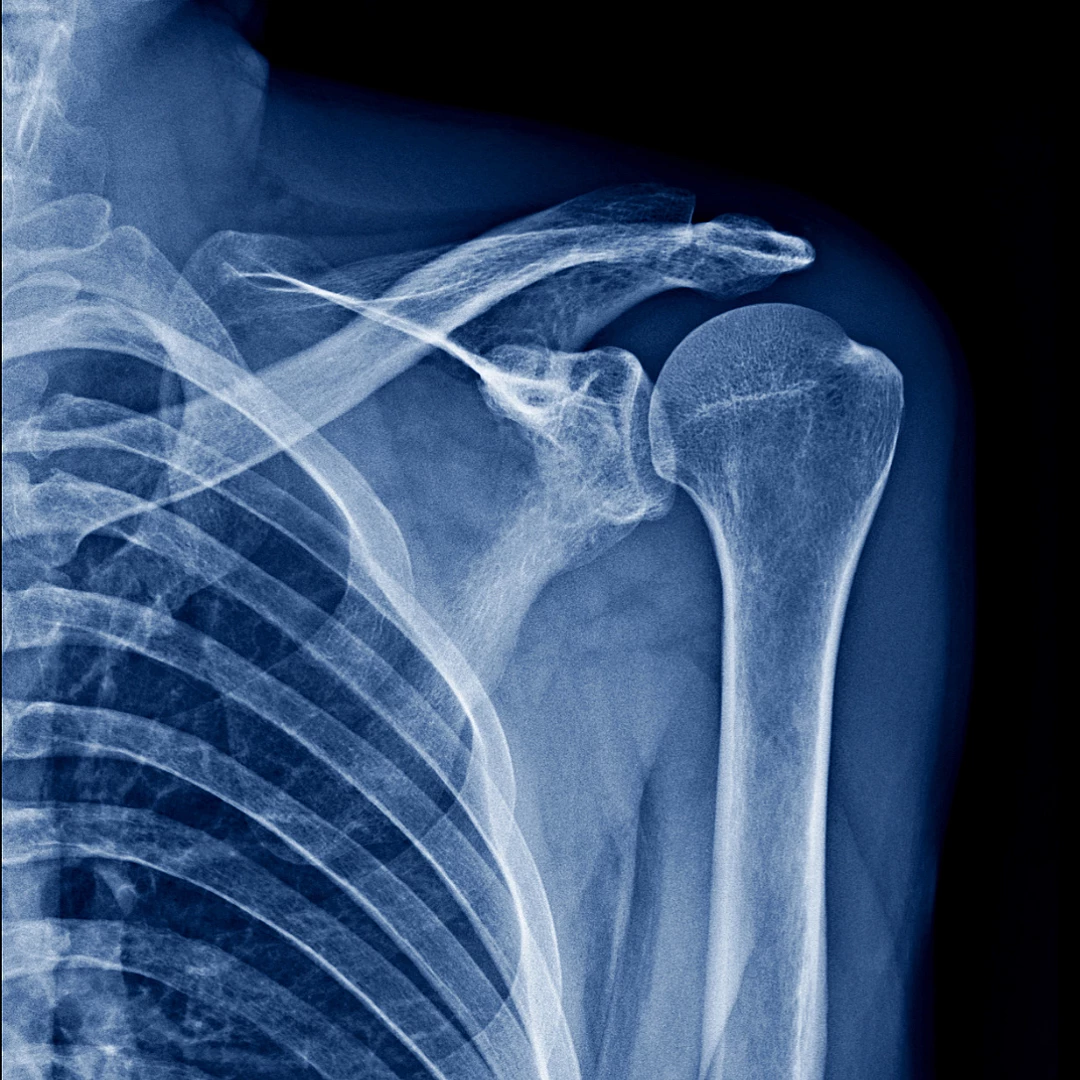

علاج خلع الكتف

خلع الكتف هو خروج عظمة الذراع العلوية من التجويف.

• قد تشمل الأعراض الألم، التورم، وانخفاض القدرة على الحركة

• من أهم أسباب الخلع الإصابة المباشرة مثل السقوط أو الإصابات الرياضية

• يعتمد العلاج على حالة المريض، طبيعة نشاطه الرياضي، وثبات الكتف

• تساعد الجراحة بالمنظار على إعادة ترميم الأنسجة وتثبيت الكتف، مما يمنع تكرار الخلع، خصوصاً لدى الناشطين في الرياضة

ترميم تمزق أربطة الكتف بالمنظار

إعادة ترميم الكفة المدورة بالمنظار هي تقنية لإصلاح الأوتار الممزقة في الكتف.

المنظار مثل تلسكوب رقيق مع مصدر للضوء يضخم الرؤية داخل المنطقة مما يسمح بالتقييم والعلاج بإستخدام الأدوات الجراحية الخاصة عبر شقوق صغيرة في الجلد.

إجراءات جراحة المنظار:

• تنظيف الأنسجة التالفة

• إزالة العظم البارز

• إعادة ترميم الأوتار المقطعة وتثبيتها إلى العظام حيثما مزقت

تعتبر جراحة المنظار ثورة علمية وتقنية حيث توفر شفاء أسرع، فقدان دم أقل، ألم أقل ومرحلة إعادة تأهيل أكثر سلاسة وبالتالي العودة إلى النشاط.